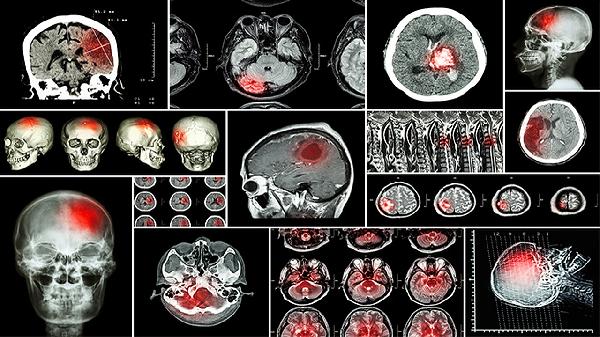

脑垂体肿瘤确实是催乳素升高的常见病理性原因,尤其是泌乳素瘤。肿瘤压迫垂体组织会导致催乳素分泌异常增高,可能伴随头痛、视力减退、月经紊乱或性功能障碍等症状。但确诊需结合垂体磁共振成像和激素动态试验,单纯依据激素水平无法直接判定。